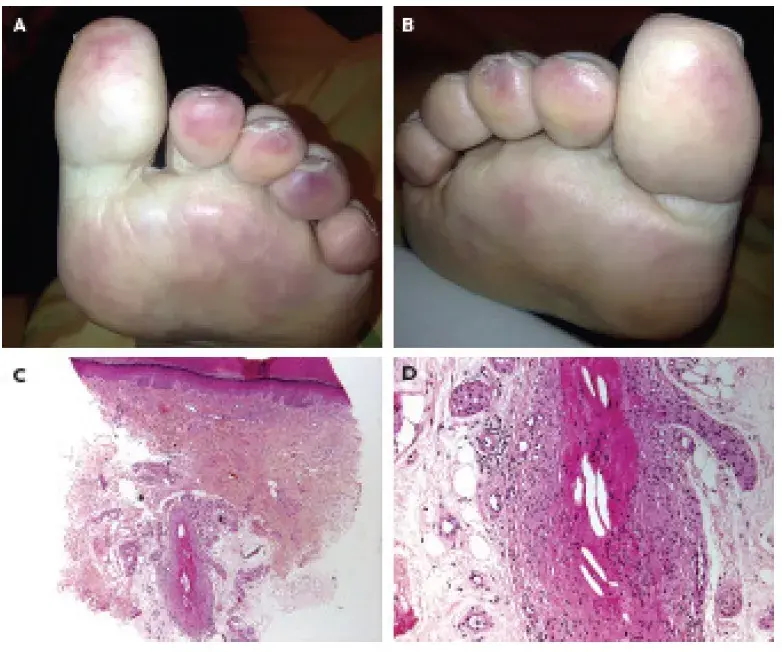

A dica é fica de olho em **PIORA DE FUNÇÃO RENAL** e **LIVEDO RETICULAR** após esses procedimentos.

- Síndrome do dedo azul